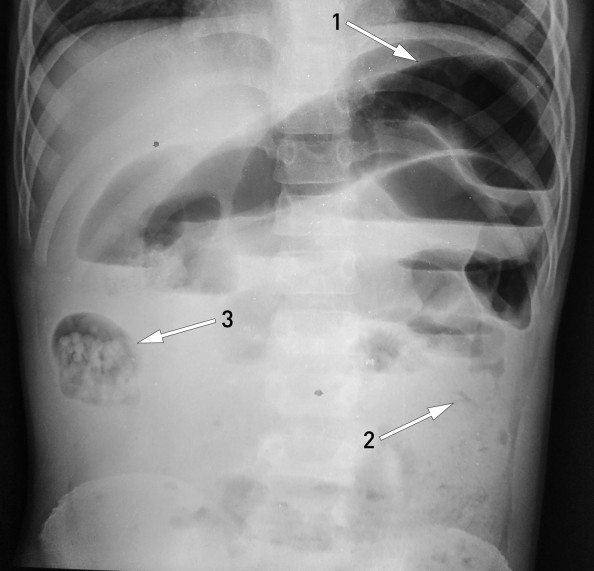

En ti år gammel gutt ble innlagt som øyeblikkelig hjelp på sykehus i et fattig område av Nepal. Han hadde betydelig forsinket lengdevekst. De siste tre dagene hadde han hatt magesmerter, oppkast og distendert abdomen. Han hadde ikke hatt avføring, men avgang av to levende spolormer per rectum. Stående røntgen oversikt abdomen (røntgenbilde) viste distenderte tynntarmsslynger (pil 1), men normal kolon (pil 2), altså funn forenelige med mekanisk tynntarmsobstruksjon. Man mistenkte at en ansamling av spolormer i et tarmsegment i høyre flanke (pil 3) – sannsynligvis i en tynntarmsslynge eller høyre hemikolon – hadde forårsaket en ileus.

Initialt hadde gutten brukbar allmenntilstand, og man valgte konservativ behandling av ileus forårsaket av spolorm, det vil si faste, intravenøs væske, antibiotika, piperazin i magesonde og klyster med glyserol og flytende parafin (1). Åtte timer etter innleggelsen ble gutten dårligere med økende smerter, abdominalomfang og oksygenbehov. Han ble derfor laparotomert. Man fant distendert tynntarm, og en incisjon ble lagt cirka midt på jejunum. Et enormt antall døde spolormer kunne melkes ut av tarmen, fra både proksimal og distal del (fotografi). Incisjonen i tarmen ble deretter lukket. Postoperativt forløp var ukomplisert, og gutten ble utskrevet i velbefinnende etter få dager.